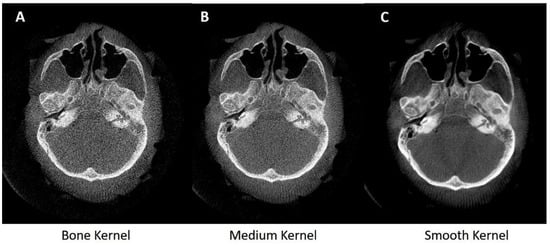

3.1.3. Kernels